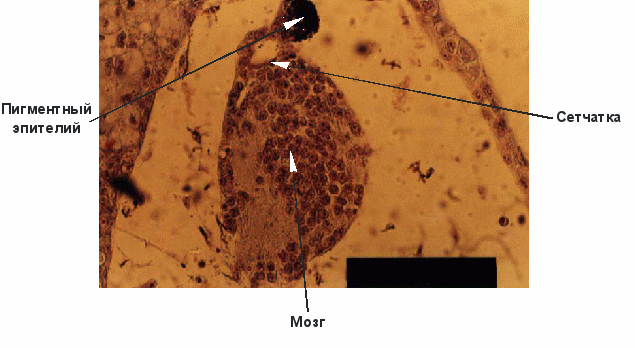

Важнейшим экспериментальным фактом явилось обнаружение способности пептидов индуцировать дифференцировку полипотентных клеток (рис. 9) [36, 38]. Так, добавление пептидов сетчатки к полипотентным клеткам эктодермы ранней гаструлы лягушки Xenopus laevis привело к возникновению клеток сетчатки и пигментного эпителия. Этот выдающийся результат в значительной степени объясняет положительный клинический эффект после применения препарата сетчатки у людей при дегенеративных заболеваниях сетчатки [27, 35, 82] и у животных с генетически детерминированным пигментным ретинитом [35, 94].

Рис. 9. Индукционное влияние пептидов сетчатки на полипотентные клетки эктодермы ранней гаструлы Xenopus laevis.

Добавление других коротких пептидов к полипотентным клеткам эктодермы в этой же экспериментальной модели приводило к возникновению различных тканей. Эти эксперименты показали, что пептиды способны индуцировать дифференцировку клеток в зависимости от структуры добавляемого вещества. Анализ результатов этих исследований дает основание сделать принципиальный вывод о возможности целенаправленной индукции дифференцировки полипотентных клеток и использования биологического клеточного резерва различных органов и тканей организма, что составляет основу увеличения продолжительности жизни до видового предела.